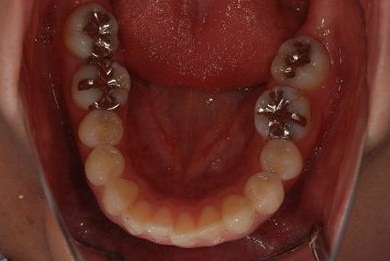

治療前

• 治療前